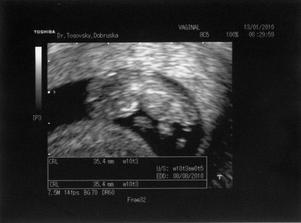

4.2.2010 UTZ - 13tt+4, měříme 76mm, NT screening ... v pořádku

25.3.2010 velký UTZ - 20tt+4, vážíme 366g ... už víme co to bude, ale zatím neříkáme - on člověk nikdy neví 🙂)